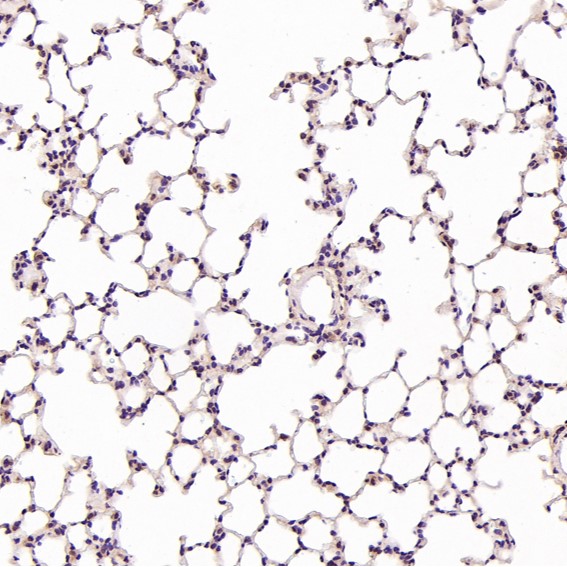

Immunohistochemical analysis of paraffin-embedded Mouse lung, using the Antibody at 1:200 dilution.